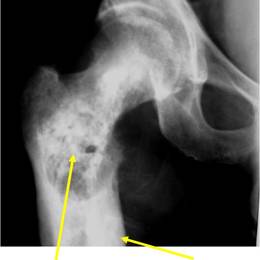

Radiographic imaging is used to help form a diagnosis. These include X-Ray, MRI, CT and Bone Scans.

An example of a dedifferentiated chondrosarcoma X-Ray is shown.